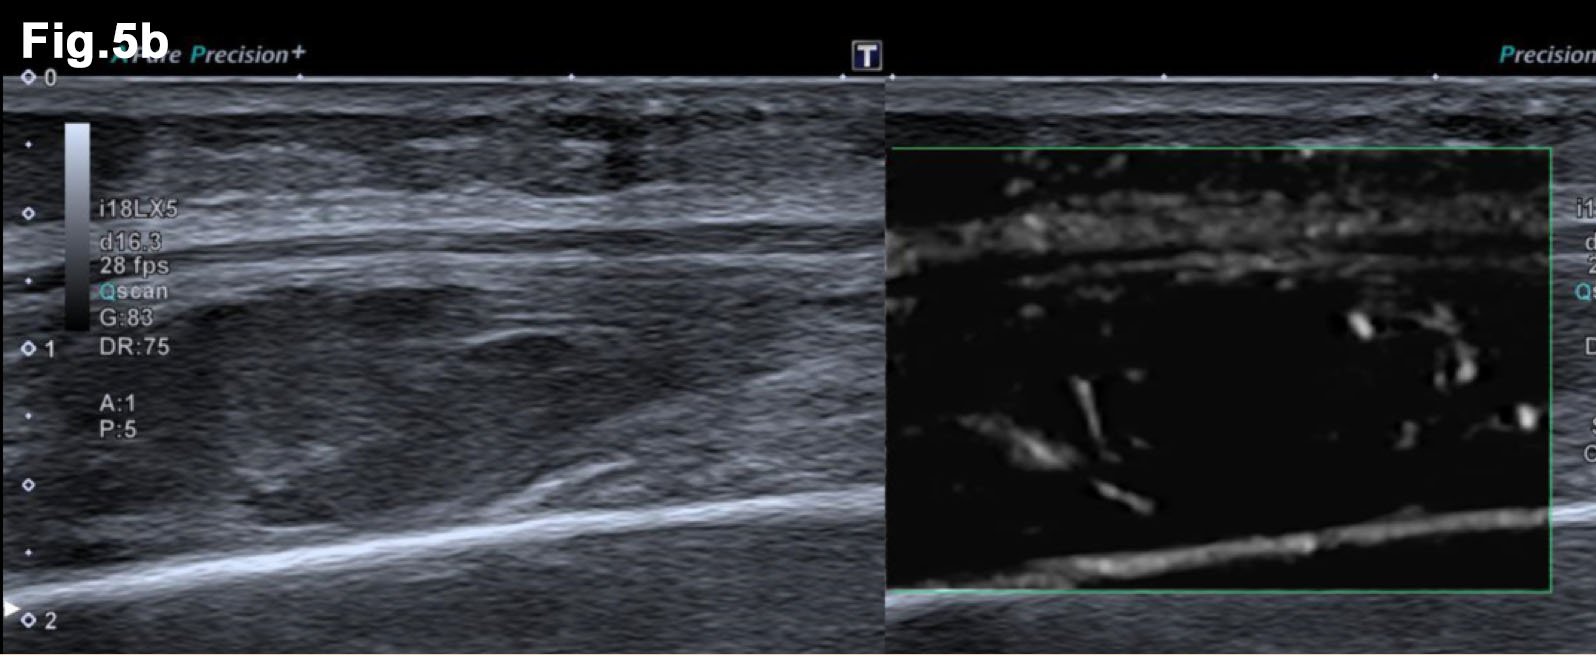

Figure 5 – New presentation of left calf pain with clinical suspicion of a deep venous thrombosis(DVT) – US demonstrated a well-defined hypoechoic mass lesion (a)with moderate vascularity (b) in left gastrocnemius. - Hypoechoic lesion in L gastrocnemius (Fig 5a) - Vascularity demonstrated on Microflow Imaging. (Fig 5b)

- MRI 2017- post chemotherapy (Figure 4)

- Both muscle lesions showed a significant reduction in size

- Recent Ultrasound 2018 (Figure 5)

- There was an irregular mass in the left gastrocnemius at the site of tenderness. It was moderately vascular and was subsequently biopsied to reveal a new metastatic deposit similar to the previous lesions and thus disease progression.